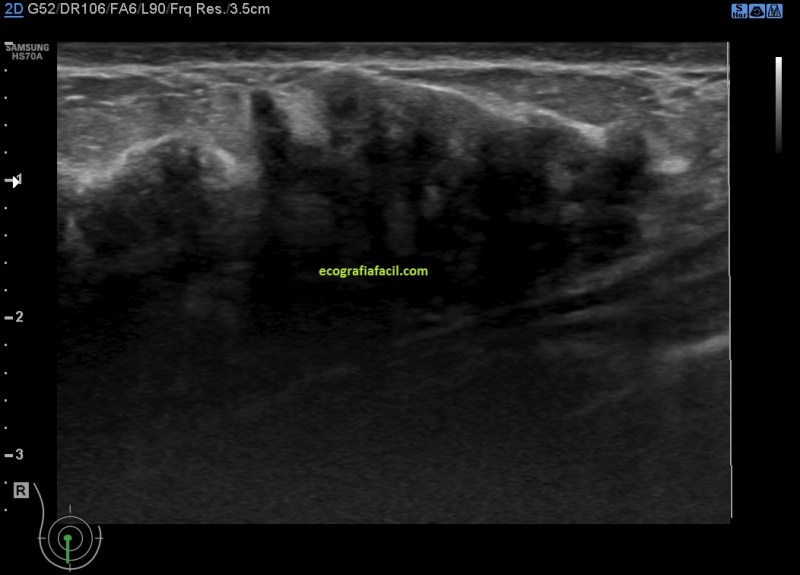

Imágenes:

2. Mastopatía

En la imagen 1 tienes la normalidad, con anatomía, que te sirva para tener una base para que puedas valorar lo que ves en las imágenes siguientes. En la imagen 2 tiene una mama de una mujer joven, con el tejido fibroso ocupando gran parte de la mama, pudiera ser una mastopatía.